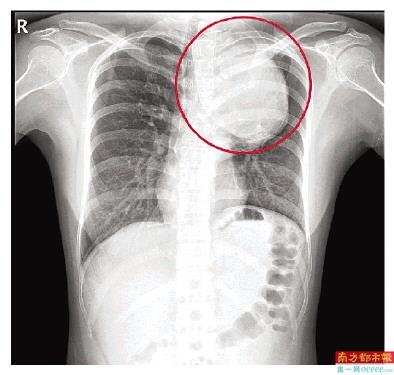

“患者的胸主动脉瘤非常大,位于主动脉弓降部,它会像吹气球一样,越长越大。正常人的主动脉弓部只有香肠那么大,而患者的主动脉瘤直径达75mm,已经有大青芒那么大了,是正常人的5倍,瘤子像一条蟒蛇一样,从颈部长到膈肌,深入隐藏在患者体内。”南方医科大学深圳医院心脏与血管外科主任杨建安说。

小茹的胸主动脉瘤已经是正常人的5倍,血管壁已经被撑得很薄,管壁只有1mm,随时可能破裂,血压一旦升高,比如生气、解大便、跑步等,都可能引起瘤子破裂,必须马上拆弹。